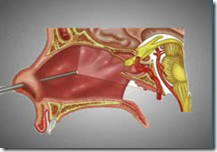

Nasal fractures are among the most typical facial accidents, typically resulting from sports activities actions, falls, or altercations. Prompt and http://wesell4youtwo.org/__media__/Js/netsoltrademark.php?d=vagas.colaboradorgolin.com.br/employer/rinoplastia-volta-redonda/ thorough evaluation by an Ear, Nose, and Throat (ENT) specialist is crucial for determining the extent of the damage and facilitating appropriate administration. This guide will explore the crucial elements of the analysis, ensuring comprehensive take care of affected peopl Understanding the systematic steps involved within the ENT evaluation of nasal fractures is essential for healthcare professionals, as it directly influences therapy choices and affected person outcomes. The evaluation process not only addresses the physical damage but in addition assesses potential complications, corresponding to airway obstruction or sinus involvement.

Nasal fractures are among the most typical facial accidents, typically resulting from sports activities actions, falls, or altercations. Prompt and http://wesell4youtwo.org/__media__/Js/netsoltrademark.php?d=vagas.colaboradorgolin.com.br/employer/rinoplastia-volta-redonda/ thorough evaluation by an Ear, Nose, and Throat (ENT) specialist is crucial for determining the extent of the damage and facilitating appropriate administration. This guide will explore the crucial elements of the analysis, ensuring comprehensive take care of affected peopl Understanding the systematic steps involved within the ENT evaluation of nasal fractures is essential for healthcare professionals, as it directly influences therapy choices and affected person outcomes. The evaluation process not only addresses the physical damage but in addition assesses potential complications, corresponding to airway obstruction or sinus involvement.By analyzing engagement metrics, conversion charges, and suggestions, you'll be able to optimize your campaigns in real-time. This process might involve altering headlines, pictures, or CTAs to see which mixture resonates extra successfully along with your audience. A/B testing lets you compare totally different versions of your ads to determine which performs higher. This iterative approach not only will increase the effectiveness of adverts but in addition helps you become extra in tune with your audience's preferences and behaviors. Implementing A/B Testing for Registro completo Optimization

CT scans present detailed photographs of nasal anatomy and may help determine associated accidents, such as fractures of the orbits or cranium base. Radiographs (X-rays) are sometimes the first-line investigation used to confirm the presence of a fracture. However, in complicated cases or within the presence of suspected sinus involvement, a CT scan may be warranted. After the initial bodily assessment, imaging research play a pivotal role within the Nasal Fractures: ENT Evaluation Steps. These imaging modalities not only facilitate accurate diagnosis but also information remedy methods, significantly in surgical plannin